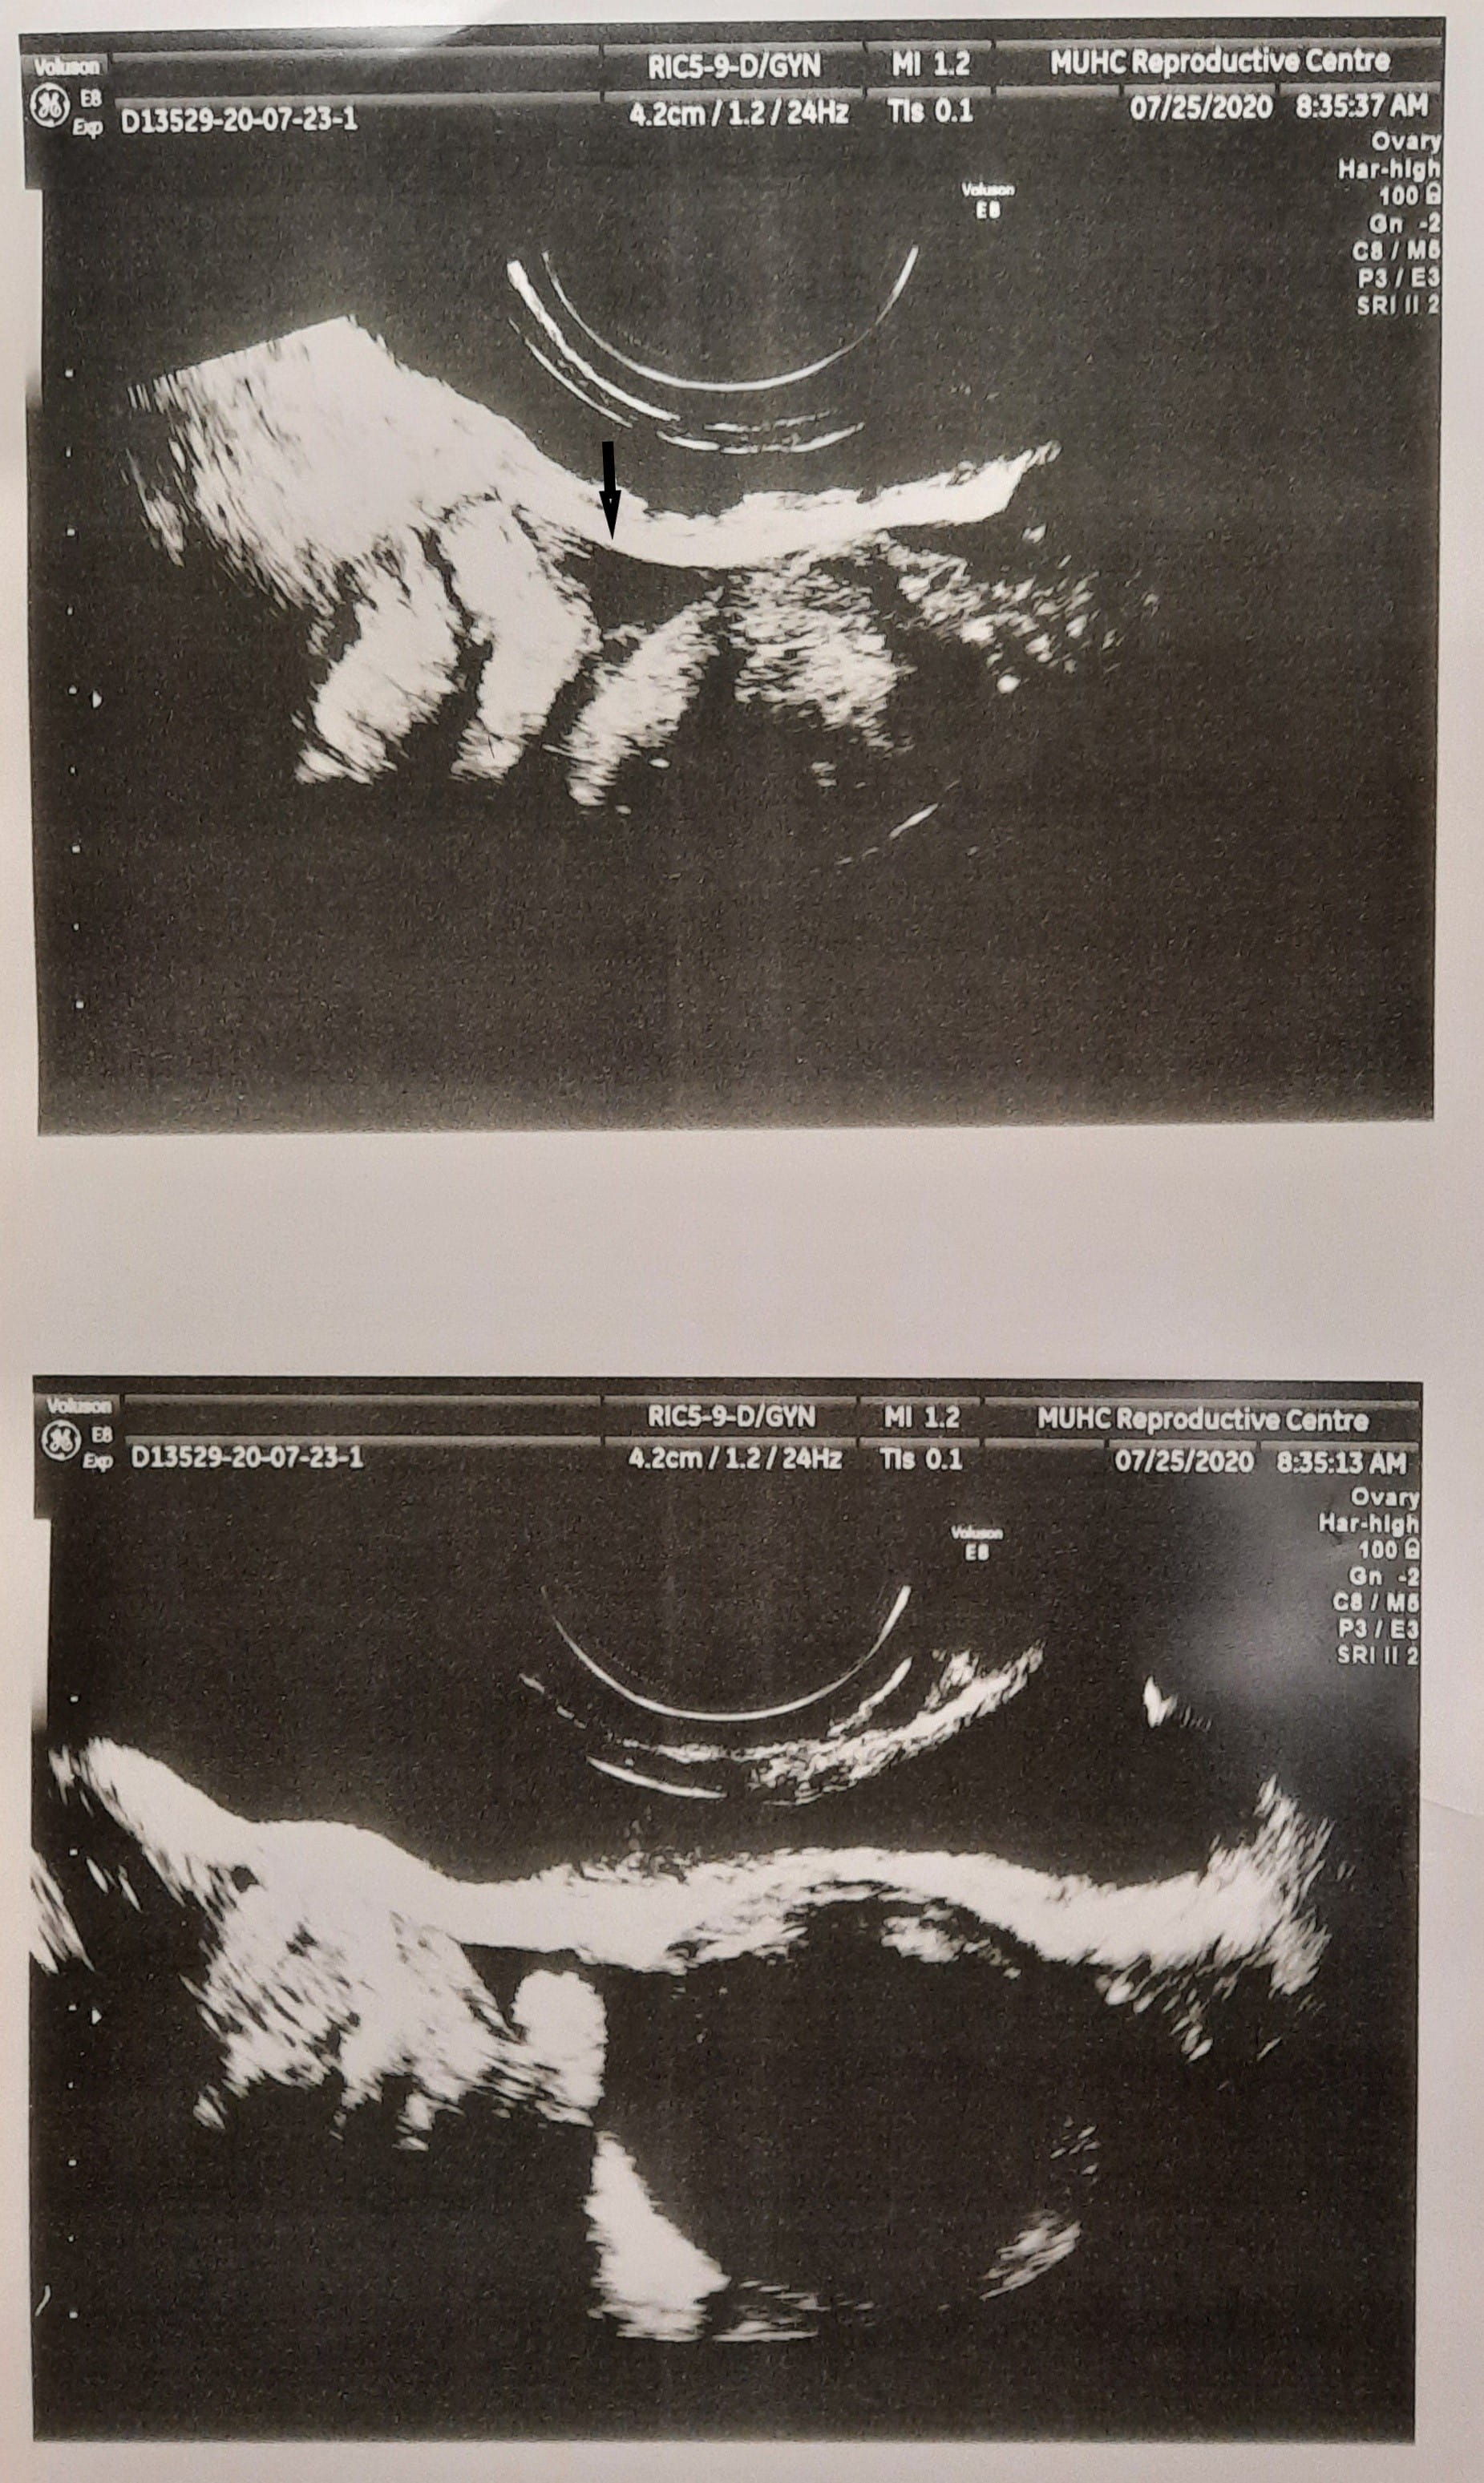

Fig. 1.Transvaginal ultrasound demonstrating subcutaneous fluid collection on the day of oocyte retrieval. (Please note the separate fluid of the urinary bladder overlying the uterine corpus as marked by an arrow).

Fertility preservation in patients suffering from borderline ovarian tumors have been described in the literature [5, 7, 16]. Gonadotropin stimulation of ovarian tumor cells could in theory cause tumor cell growth and metastasis to occur. However, up until this point no proof of such has been noted. This was assumed to be due to the short duration of gonadotropin stimulation. However, this is the first time in the medical literature that a supra-facial large fluid collection occurred during ovarian stimulation of an ovarian tumor patient, with the absence of ascites or ovarian hyperstimulation syndrome. The subject had only 4 follicles stimulated, relatively low serum estradiol levels and no ascites was present. It is also extremely unlikely that ovarian hyperstimulation syndrome was present on the day of oocyte retrieval because it usually occurring several days latter. Interestingly, the fluid collection was self-limited and disappeared post ovarian stimulation. Regrettably, this occurred prior to obtaining a cytological specimen of this fluid for assessment. Our hypothesis is that during the emergency operation for the cyst rupture, before the stimulation cycle started, low malignant potential ovarian cells spread via the laparoscopy port to the subcutaneous space, although of such we cannot be certain.